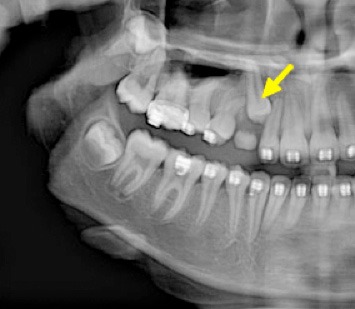

Dientes Supernumerarios

Los dientes supernumerarios son dientes adicionales que pueden aparecer en la boca y causar problemas de alineación o erupción de otros dientes.

Los pacientes pueden notar dientes adicionales en la boca, lo que puede causar apiñamiento o problemas estéticos.

El tratamiento incluye la extracción quirúrgica de los dientes supernumerarios.